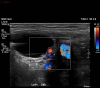

We report the case of a 32-year-old woman who presented with reducible indirect inguinal hernia and a challenging constellation of symptoms, signs and radiographic findings. Surgical approach superseded conservative management when the patient's abdomen became acute, with a rising lactate and haemodynamic instability. Specifically, the presence of a fluid collection was concerning for sinister acute pathology. Our patient was rediagnosed intraoperatively with hydrocoele of canal of Nuck. This so-called 'female hydrocoele' is an eponymous anatomical rarity in general surgery, presenting as an inguinolabial swelling with variable clinical profile. Hydrocoele of canal of Nuck takes origin from failure of transitory reproductive anlagen to regress and is thus analogous to patent processus vaginalis. Its true incidence is speculative, with just several hundred cases globally. We aim to provide insights into surgical patient management for a rare entity during the COVID-19 outbreak, from the unique perspective of a small rural hospital in Scotland.